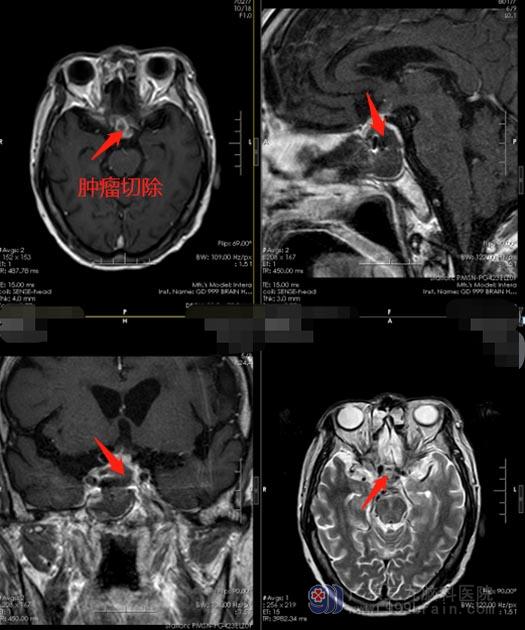

与家属充分沟通后,鲁明带领团队为李爷爷在全麻下行“经鼻碟鞍区占位切除术”。术后,李爷爷神志清醒,四肢肌力肌张力正常,由于视神经压力排除,李爷爷的眼睛已经恢复了光感。看到爷爷的情况一天比一天好,家人都非常的满意。

出现了垂体瘤卒中,及时进行手术治疗是必须的,因为垂体瘤卒中之后,伴随瘤内出血逐渐增多,如果再发生第二次或者第三次出血,造成颅内压力更加升高,血肿非常有可能破除鞍区,从而向整个颅腔内蔓延,引起更加严重的后果。